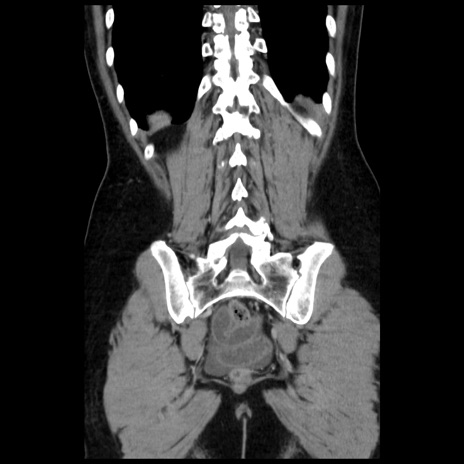

症例10(冠状断像)

【症例】 50歳代女性

【主訴】 腹痛

【現病歴】前日生レバーを食べた。今朝に排便あり。 昼前に突然発症の腹痛を生じ、当院救急外来を受診した。

【既往歴】 子宮筋腫にてで子宮全摘後

【身体所見】 意識清明、腹部:平坦、軟、下腹部やや左を中心に圧痛・反跳痛あり、筋性防御あり

【データ】WBC 7800、CRP 0.07